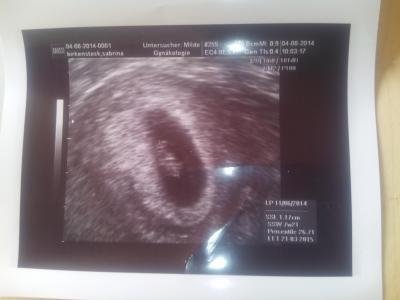

Alles super Et ist an m. Geburtstag :-) Ausser muss Tabletten nehmen wegen der schwangerschaftsvergiftung 2013 un muss den geburtsbericht besorgen nurbekomm keinen vom alten FA un muss die Klinik anrufen da geht keiner ran

Bild zu happy et 21.3 - Forum für März - Mamis